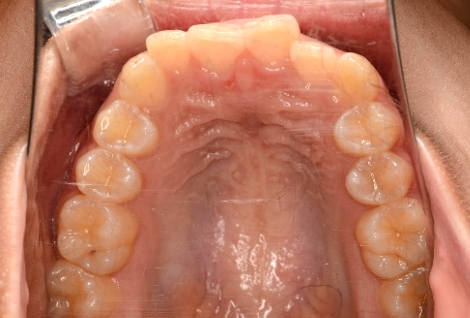

当院での部分矯正の症例

「デコボコ(叢生)」を詳しく見る